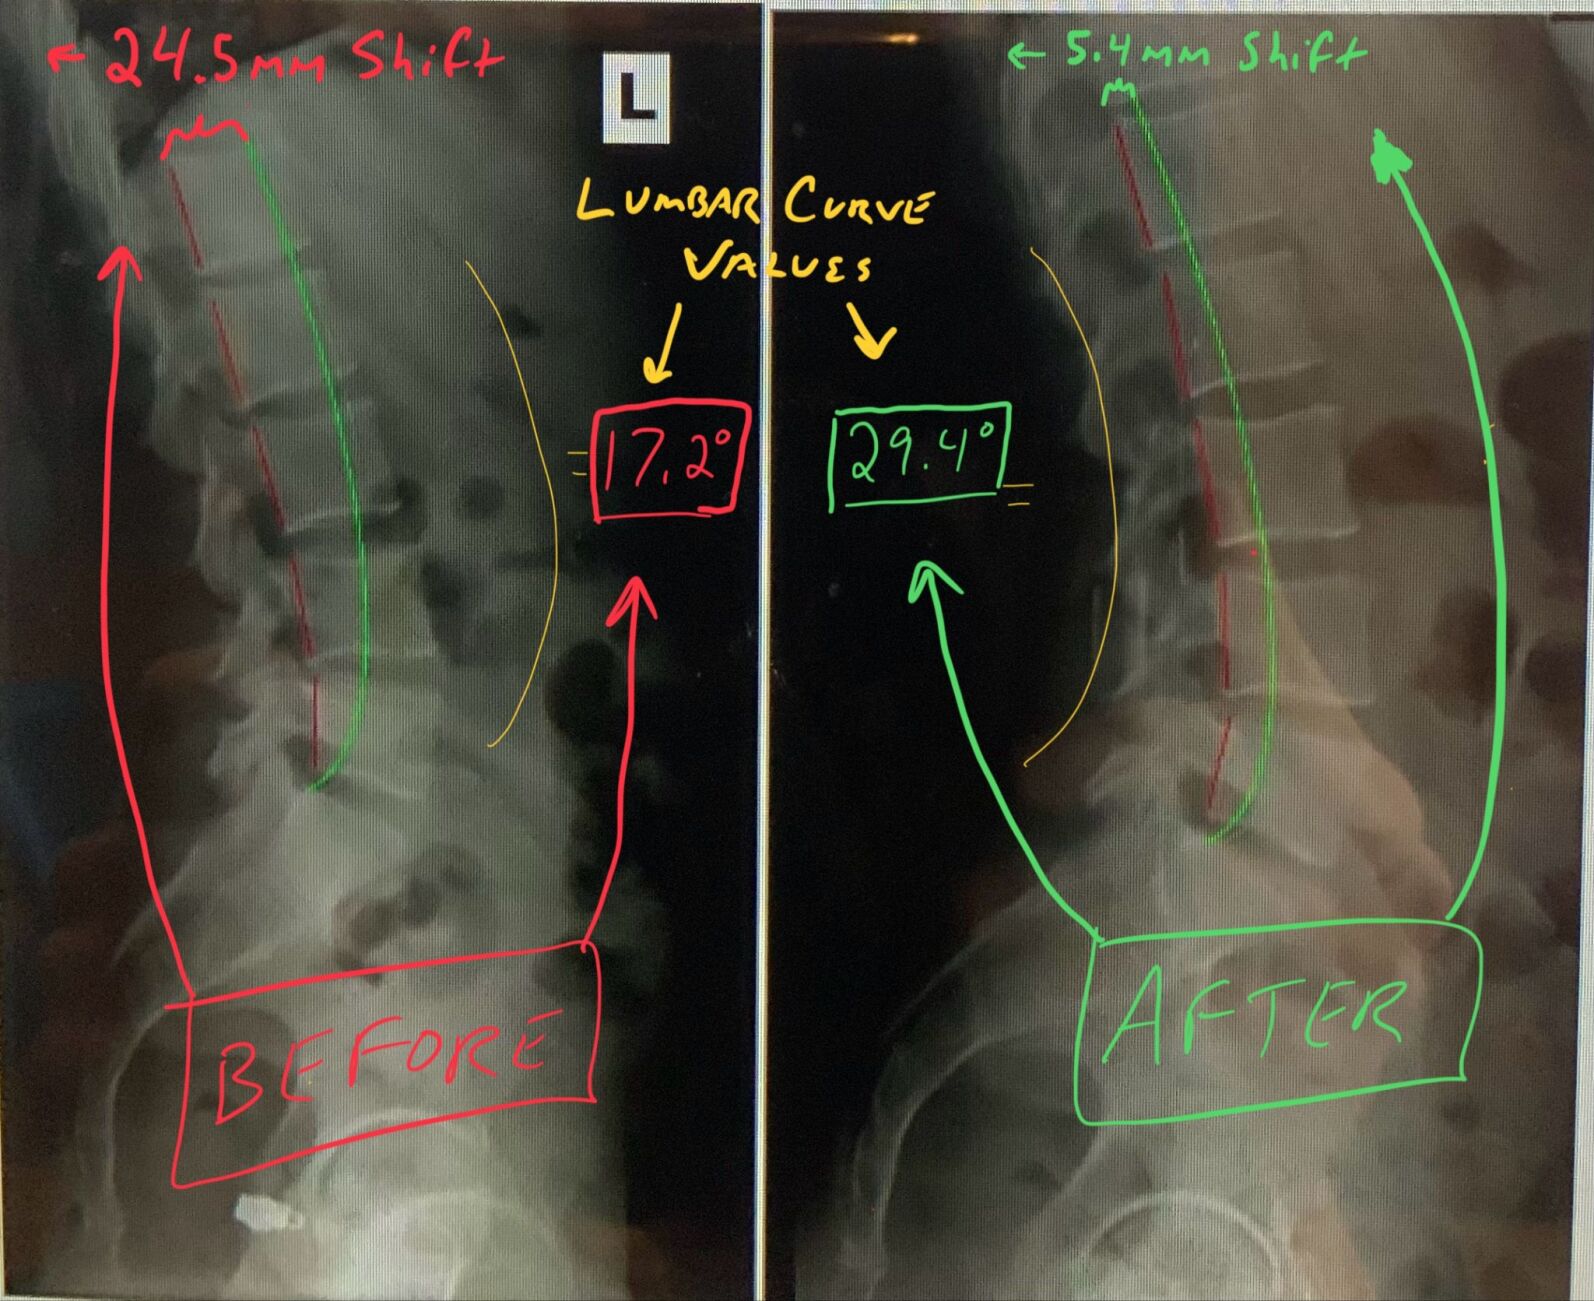

Lateral lumbar X-rays, pre and post-treatment give an example of hypolordosis (left) and a corrected (right). This patient required approximately 30 degrees of correction to match a normal lumbar curve. (COURTESY IMAGE)